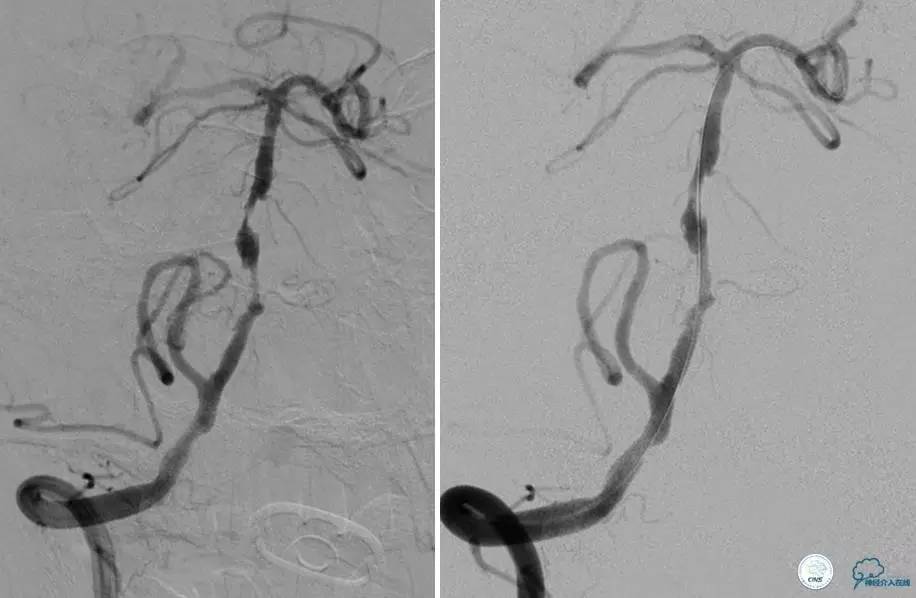

▼DSA示右侧椎动脉发育低下,弥漫性狭窄,可以看到左侧椎动脉反流,因此判断左侧椎动脉V4段CTO。

治疗:

微导丝穿过闭塞段,微导管造影,球扩闭塞段,置入Wingspan支架,血流完全恢复正常。

患者术后2天再次出现卒中发作,药物治疗好转,此后病情稳定。半年后复查DSA,见支架闭塞,侧支循环开放。患者一般情况好,mRS:1分。